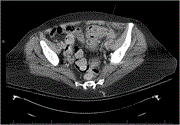

Intestinal obstruction, obturator hernia, and/or colonic neoplasms: a case study

Zhaofang Jin and Jianjun Lai

Journal of Surgical Case Reports, Volume 2023, Issue 10, October 2023, rjad583, https://doi.org/10.1093/jscr/rjad583